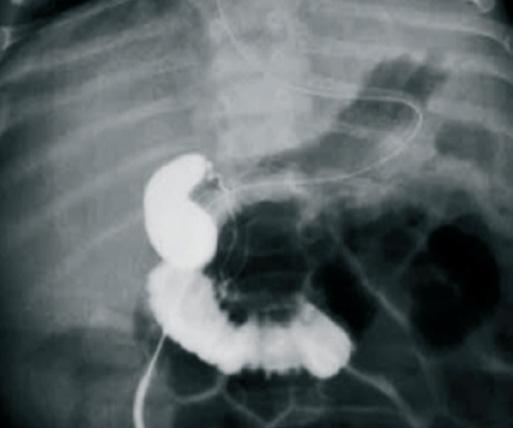

Figura

stenza di ittero e feci ipocoliche. Viene eseguita quindi una colangiografia transepatica che mostra una colecisti a contenuto acolico, comunicante con una struttura ovalare dell’ilo epatico identificata come coledoco, che tuttavia non comunica con le vie biliari intraepatiche né col tubo digestivo [Figura 4]. Le VBI sono irregolari, contengono dei microcalcoli e non sono cateterizzabili. Si pone diagnosi di atresia biliare atipica [Figura 5] [3].

4. Colangiografia transepatica che mostra una colecisti a contenuto acolico, comunicante con una struttura ovalare dell’ilo epatico identificata come coledoco, che tuttavia non comunica con le vie biliari intraepatiche e col tubo digestive.

5. Colangiografia transepatica che mostra VBI sono irregolari, contengono dei microcalcoli e non sono cateterizzabili.